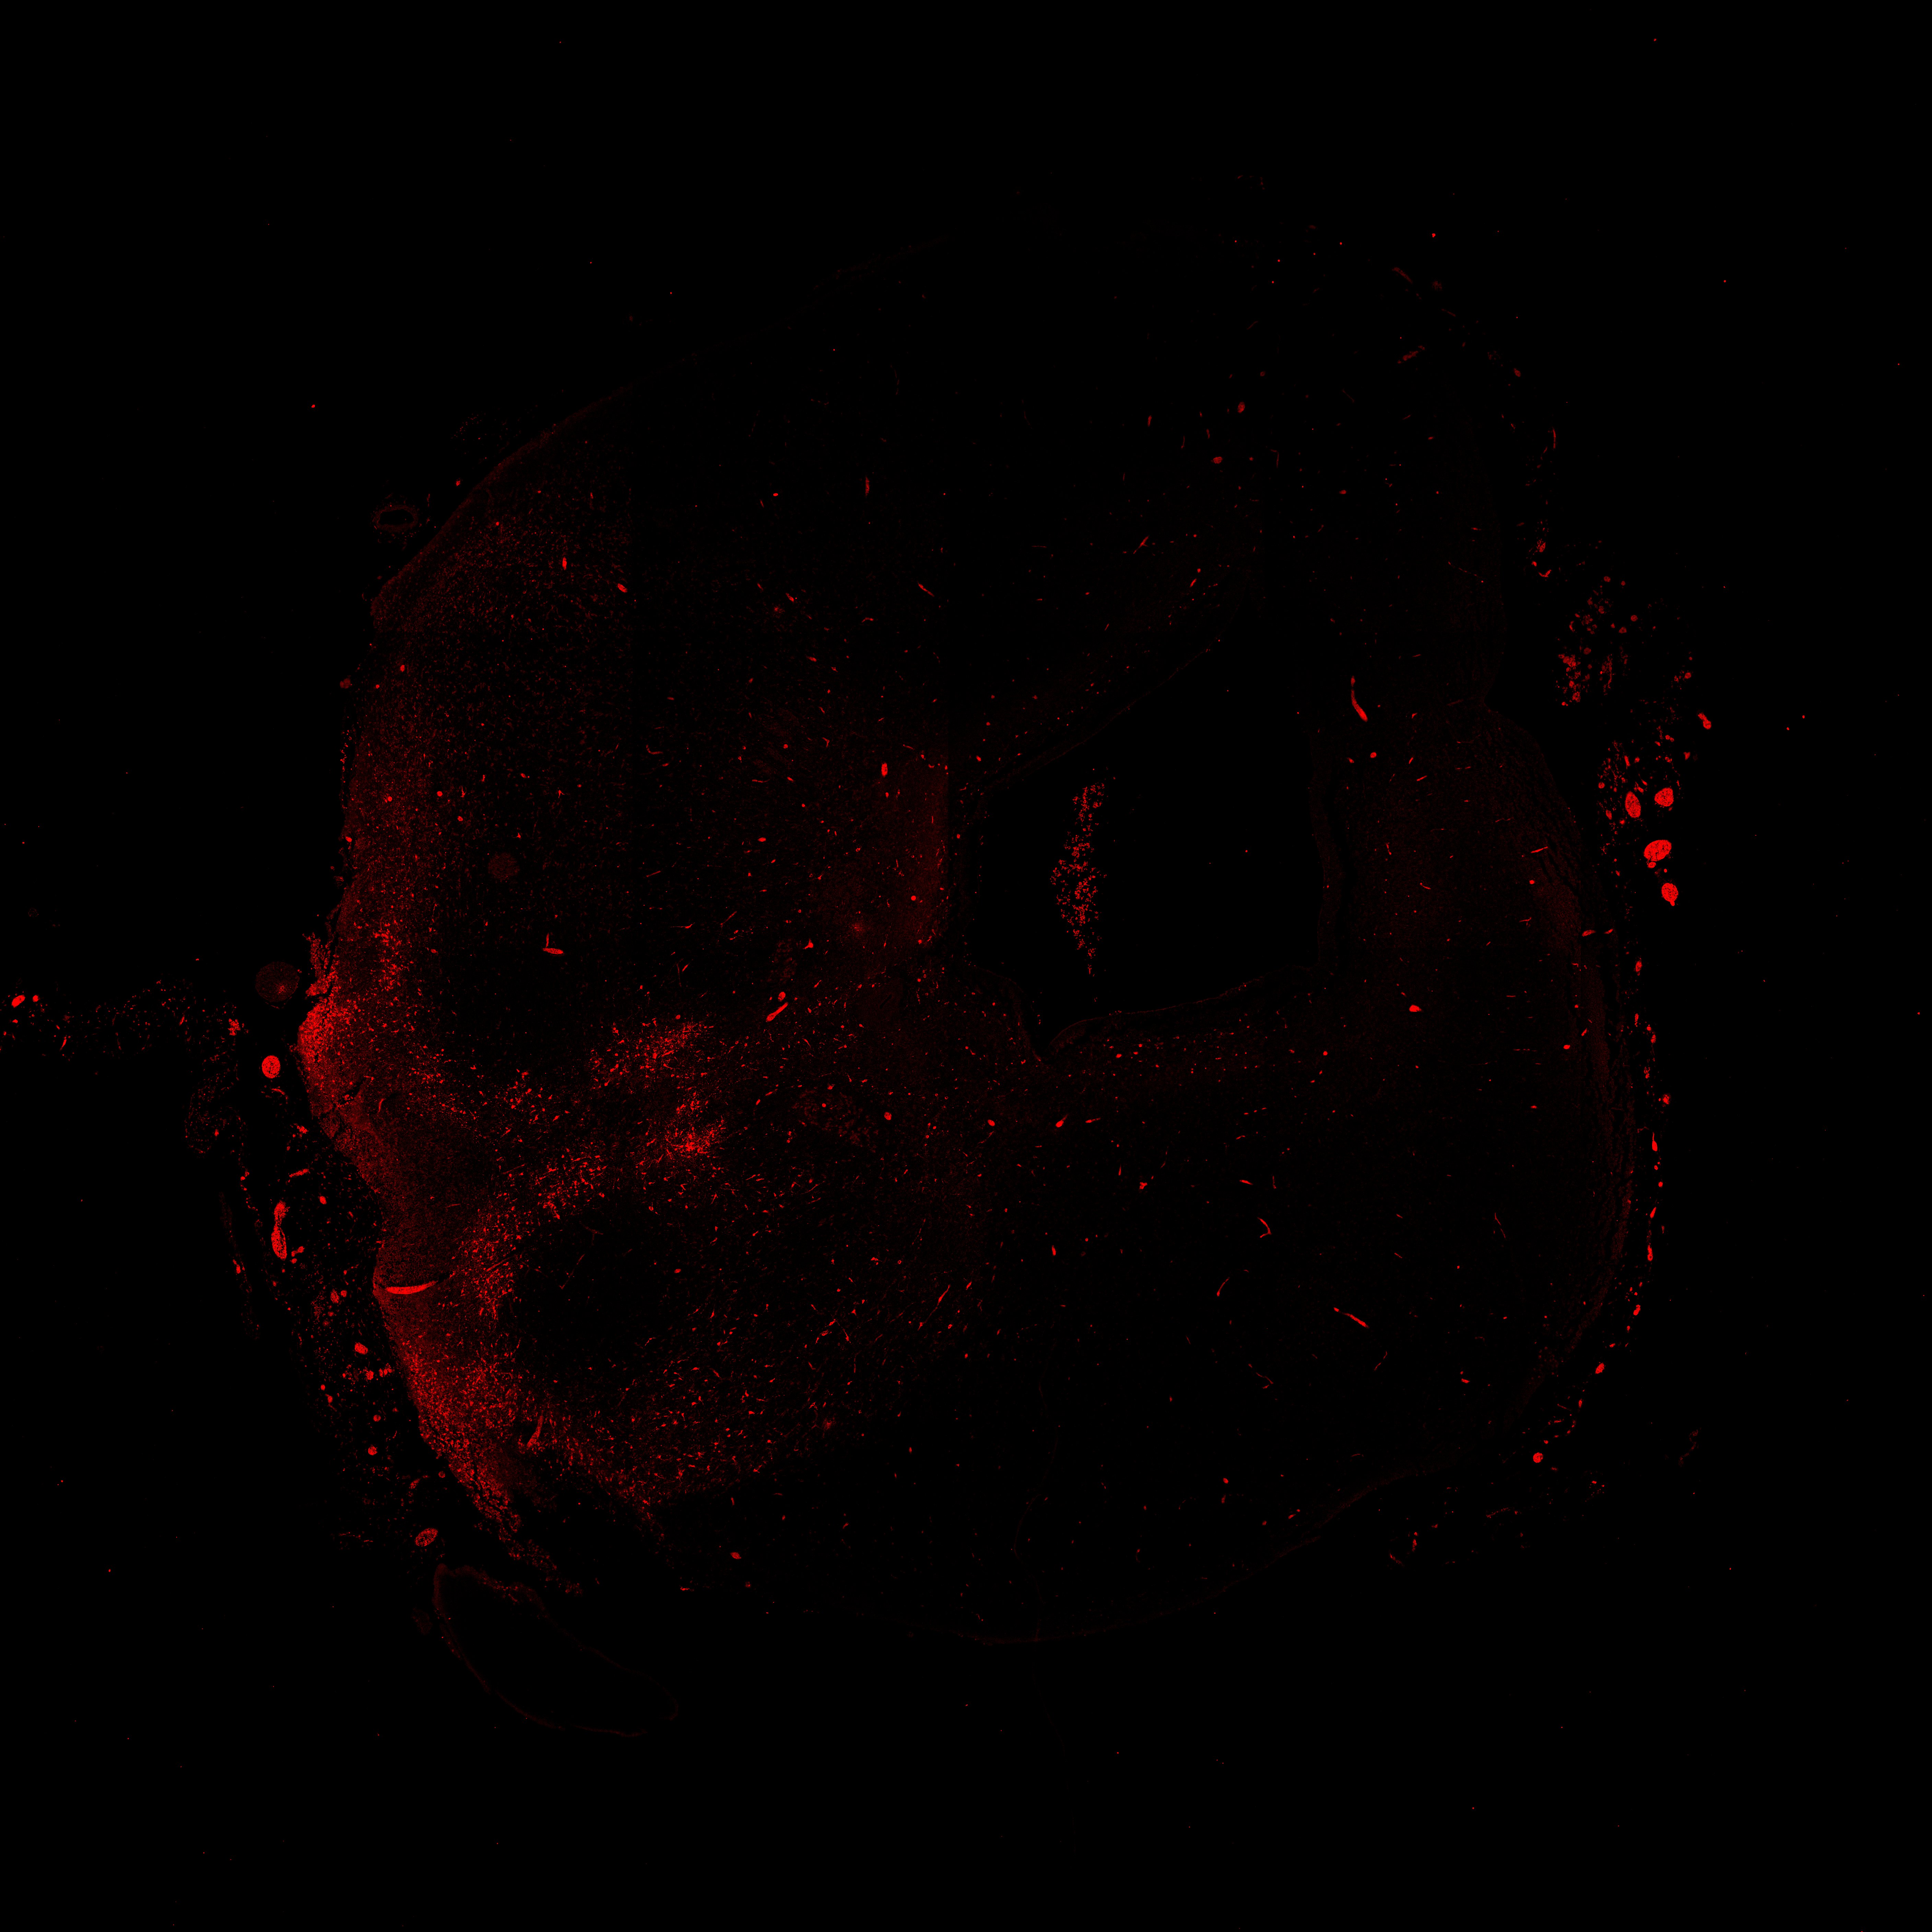

An anatomical analysis of the developing human midbrain from 6 post-conceptional weeks (PCW) to 22 PCW reveals increased tissue complexity, characterized by the emergence of dopaminergic nuclei, as highlighted by immunofluorescence analysis for tyrosine hydroxylase (TH).

TH

13PCW human midbrain